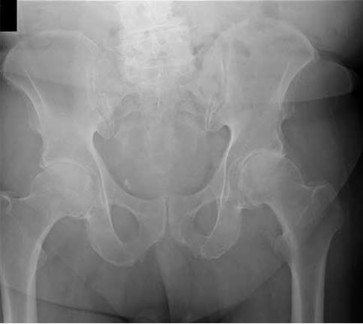

A 28-year-old female is brought to the trauma bay after a high-speed motor vehicle collision. She is hypotensive and tachycardic. A pelvic radiograph is obtained. It demonstrates a symphyseal diastasis of 3.5 cm and widening of the anterior sacroiliac joints bilaterally. Which of the following describes the status of the posterior pelvic ligaments in this specific injury pattern?

Options:

Correct Answer: The anterior sacroiliac ligaments are disrupted, but the posterior sacroiliac ligaments remain intact.

Explanation:

The clinical scenario describes an Anteroposterior Compression Type II (APC-II) pelvic ring injury. By definition, an APC-II injury involves disruption of the pubic symphysis (typically >2.5 cm) along with tearing of the anterior sacroiliac, sacrotuberous, and sacrospinous ligaments. The critical distinguishing factor of an APC-II injury from an APC-III injury is that the strong posterior sacroiliac ligaments remain intact, providing vertical stability while allowing rotational instability.